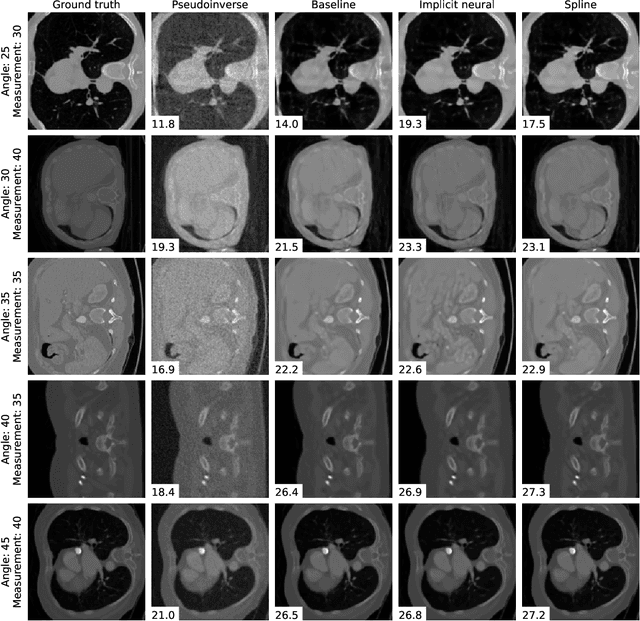

Abstract:We propose a differentiable imaging framework to address uncertainty in measurement coordinates such as sensor locations and projection angles. We formulate the problem as measurement interpolation at unknown nodes supervised through the forward operator. To solve it we apply implicit neural networks, also known as neural fields, which are naturally differentiable with respect to the input coordinates. We also develop differentiable spline interpolators which perform as well as neural networks, require less time to optimize and have well-understood properties. Differentiability is key as it allows us to jointly fit a measurement representation, optimize over the uncertain measurement coordinates, and perform image reconstruction which in turn ensures consistent calibration. We apply our approach to 2D and 3D computed tomography and show that it produces improved reconstructions compared to baselines that do not account for the lack of calibration. The flexibility of the proposed framework makes it easy to apply to almost arbitrary imaging problems.